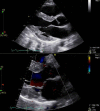

Belhassen tachycardia is the most common idiopathic ventricular tachycardia arising from the left ventricle, classically characterized by a right bundle branch block and left axis deviation. Vigilance for Belhassen tachycardia is essential as intravenous verapamil has proven to be highly efficacious for treating symptomatic patients with this underlying arrhythmia.